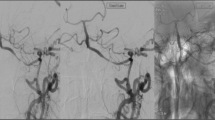

On day 28, due to progressive aphasia and weakness, the patient was taken for endovascular treatment, the first of seven such treatments performed (detailed in Table 1). In each case, the decision to treat was driven by severe vessel stenosis (≥ 70%) and one or more of the following: new ischemic lesions on MRI (treatments 1, 2, 5, 7), prolonged CT perfusion Tmax (treatments 3, 4), or abrupt decline in neurologic examination (treatments 1–5, 7). Sub-maximal PTA was performed using coaxial guide catheter support with either the Cook Shuttle 6 Fr Sheath or Benchmark 0.071″ guide catheter and the Gateway Balloon System (Stryker Neurovascular, Kalamazoo, MI, USA) with gradual inflation (~1 atm. per 15–30 s) to nominal pressure (6 atm.). An angiographic result of < 50% stenosis was considered technically successful. In each case, delayed (15 min) angiography was performed after PTA to confirm absence of dissection and acute restenosis. A small, non-flow limiting dissection occurred after the first PTA of LICA (Fig. 2f); based on this complication, the decision was made to defer post-PTA stent placement in subsequent treatment sessions as the additional risk conferred by stenting was felt to be prohibitive. Dual antiplatelet therapy (aspirin 81 mg and clopidogrel 75 mg) was initiated at this time with concurrent gastrointestinal mucosal protection (famotidine 20 mg, daily).

Intracranial manifestations of giant cell arteritis with left ACA-MCA watershed ischemia on DWI MRI (a). Time-of-flight MR angiography showed high-grade stenosis of supraclinoid LICA (white curved arrow, b). CT perfusion showed at-risk parenchyma throughout the left hemisphere, shown as Tmax map (c) which prompted urgent endovascular treatment (treatment #1). Pretreatment lateral projection LICA injection shows 2 sites of critical stenosis (d, white arrows) which were treated with submaximal balloon angioplasty (e). Posttreatment result f showed substantial improvement in angiographic transit time and return of antegrade flow to the ophthalmic and posterior communicating arteries. Careful review of images showed a tiny, non-flow limiting dissection measuring < 1 cm (red arrow)